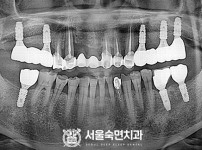

상악동거상술, 뼈이식 / 숙면임플란트 14개 - 네오임플란트 (이*현님)

해당 게시물은 의료법 제56조에 의거하여 로그인 후 열람이 가능합니다.

구분 임플란트